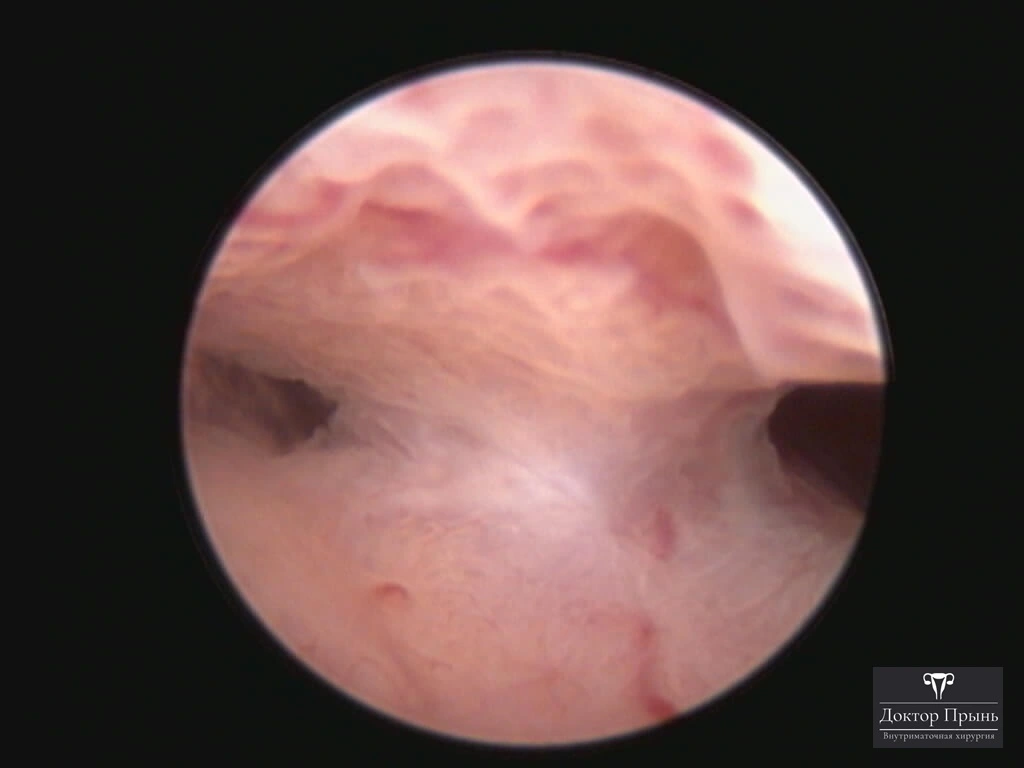

Это спайки в полости матки, которые возникают после внутриматочных вмешательств: выскабливаний, особенно после родов, абортов, удаления субмукозной миомы. Степень выраженности спаек варьируется от единичных лёгких перетяжек до полного заполнения полости матки плотной рубцовой тканью. Также спайки появляются в цервикальном канале.

Как правило, синехии находят при УЗИ. Когда по УЗИ патологии нет, а симптомы есть, выполняют гистероскопию – это золотой стандарт в определении синехий.

Гистероскопия позволяет не только увидеть спайки, но и сразу вылечить, т.е. рассечь их. Большинству пациенток подойдёт офисная гистероскопия без наркоза и госпитализации. Среднее время операции 15 минут. Иногда требуется 2-4 операции, чтобы восстановить полость матки.

Крайне важен способ разделения спаек. Если это холодный инструмент, например, ножницы, то вероятность рецидива низкая. Плюс не повреждается нормальный эндометрий. Если рассекают горячей электропетлёй, то, наоборот, риск рецидива высокий и можно обжечь эндометрий.

Фотогалерея

Синехии, рассечённые Прынь Д.В.